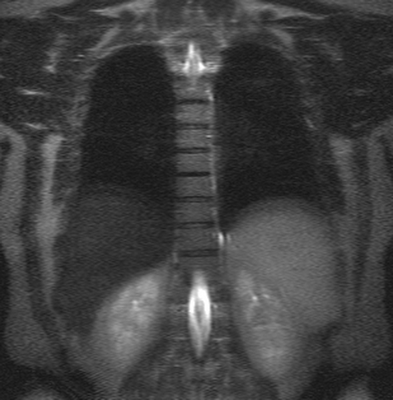

Грудной отдел позвоночника на МРТ в коронарной проекции